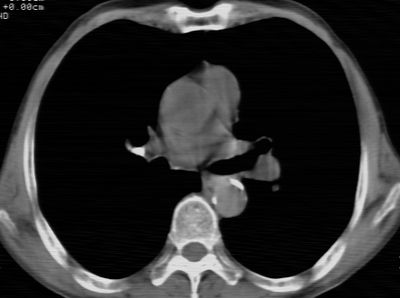

标题: CT24783:m71,既往肺心病史3年,现咳嗽,憋喘。 [打印本页]

标题: CT24783:m71,既往肺心病史3年,现咳嗽,憋喘。

1、左肺上叶spn,毛刺+分叶+血管集束征,考虑周围型肺癌可能性大

2、全小叶性肺气肿。

1)左肺上叶周围型肺癌可能。2)两肺全小叶型肺气肿。

左上周围型肺癌,全小叶型肺气肿。